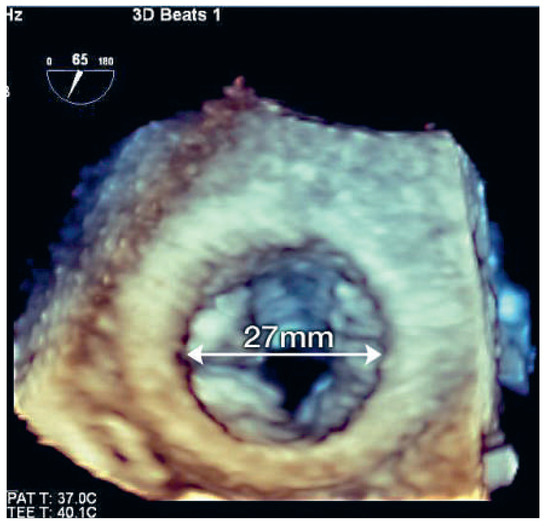

A 41-year-old women with Ebstein’s anomaly required tricuspid valve replacement six years ago. At that time a biological prosthesis was implanted. The tricuspid valve prosthesis became severely stenotic within five years. Instead of re-do surgery, th...